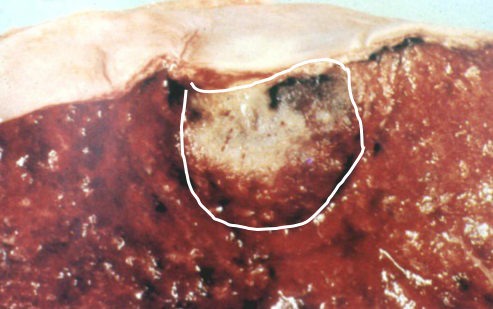

结核坏死灶由于含脂质较多呈淡黄色、均匀细腻,质地较实,状似奶酪,故称干酪样坏死(caseous necrosis)。镜下为红染无结构的颗粒状物。干酪样坏死对结核病病理诊断具有一定的意义。干酪样坏死物中大都会有一定量的结核杆菌,可成为结核病恶化进展的原因。

干酪样坏死型可见明显干酪样坏死和死骨形成。病变常累及周围软组织,引起干酪样坏死和结核性肉芽组织形成。坏死物液化后在骨旁形成结核性“脓肿”,由于局部并无红、热、痛,故又称“冷脓肿”。病变穿破皮肤可形成经久不愈的窦道。

脊椎结核是骨结核中最常见者,多见于第10胸椎至第2腰椎。病变起自椎体,常发生干酪样坏死,以后破坏椎间盘和邻近椎体。由于病变椎体不能负重而发生塌陷,引起脊椎后突畸形。如病变穿破骨皮质可在脊柱两侧形成“冷脓肿”,或沿筋膜间隙坏死物下流,在远隔部位形成“冷脓肿”。